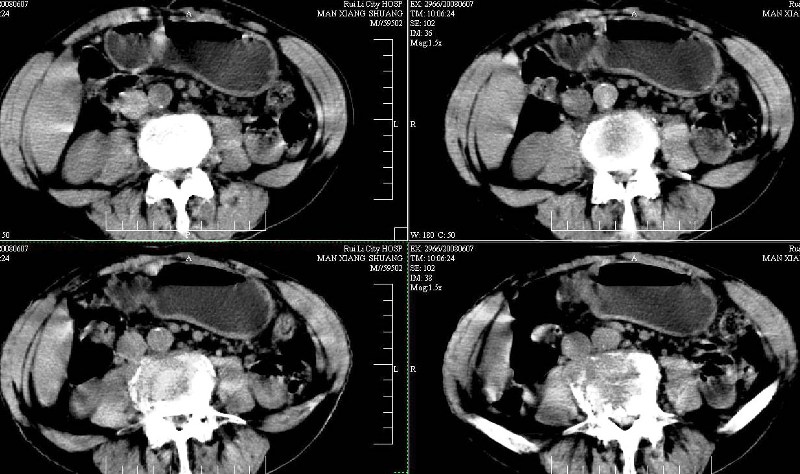

标题: CT13937:M,42A.腰疼一周。 [打印本页]

标题: CT13937:M,42A.腰疼一周。

ct(椎间盘扫描):椎间盘炎,建议dr。

dr:l4骨质破坏,转移可能。

胸部摄片未见异常。临床医生体检发现上腹部饱满。

ct:肝癌腰椎转移。临床医生:肝脏、骨转移,肿瘤来自?前列腺?!

建议强化观察肝内病灶特点,考虑肝癌骨转移。

支持肝癌伴椎体转移瘤。腹膜后建议ct增强,好象有增大的淋巴结。

1、支持肝癌肝内及腰椎转移。

2、肝脏内好象有多个病灶,建议增强检查。